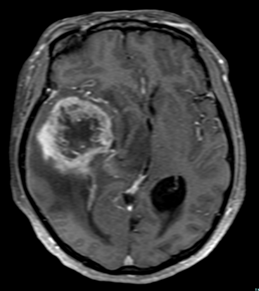

比較的に短時間で撮影できるCT検査や、より精密に調べることのできるMRI検査を行います。疑わしい場合は造影剤を使用します。画像診断は脳腫瘍の治療方針を決定するうえでも非常に重要です。診断が難しい場合や稀な脳腫瘍の場合は生検術(組織採取)を行って病理検査で診断をつけることもあります。

造影MRI検査

② 脳実質内に腫瘍(神経膠腫)を認める